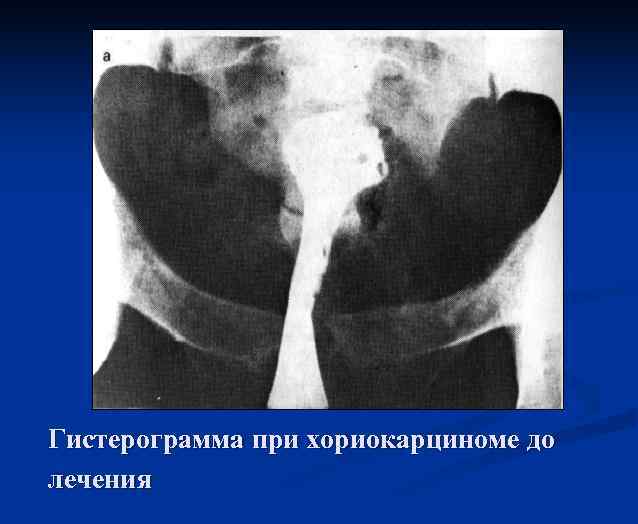

Рентгенологические методы исследования Гистерограмма при хориокарциноме, выполняющей полость матки

Гистерограмма при хориокарциноме до лечения